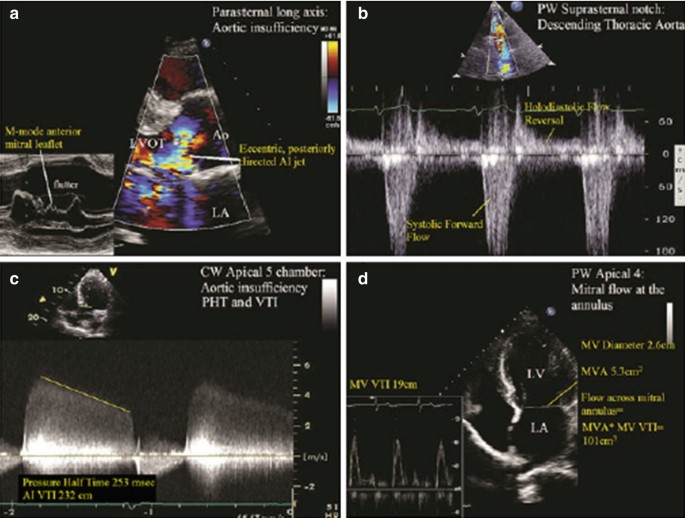

Application Of The Proximal Flow Convergence Method To Calculate The Effective Regurgitant Orifice Area In Aortic Regurgitation Sciencedirect